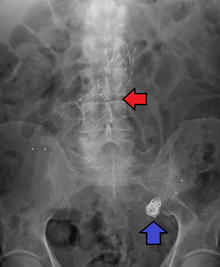

Illustration depicting location of abdominal aneurysm

Abdominal aortic aneurysm involves a regional dilation of the aorta and is diagnosed using ultrasonography, computed tomography, or magnetic resonance imaging. A segment of the aorta that is found to be greater than 50% larger than that of a healthy individual of the same sex and age is considered aneurysmal.[10] Abdominal aneurysms are usually asymptomatic but in rare cases can cause lower back pain or lower limb ischemia.